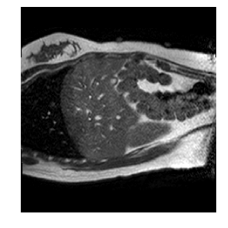

With this motivation, [6] proposed a convolutional neural network (CNN) based approach for temporal interpolation of navigators. Their CNN takes as inputs a fixed number of acquired images and learns to predict the missing images directly in the intensity space. This approach, which we call the Simple Convolutional Interpolation Network (SCIN), is a ’black-box’ formulation that does not incorporate any prior information about the interpolation process. Image prediction is guided only by the cost function used to optimize the network parameters. The issue with this is that it is unclear whether the image similarity measures that are generally used as cost functions suffice to ensure fidelity of the generated images to the original images. Indeed, Fig. 1b shows a case where an image interpolated using SCIN is quite blurry and misses several liver and lung structures present in the original image.

(a)                                (b)                                (c)

Figure 1: (a) Ground truth and (b,c) interpolated images from (b) baseline (SCIN) and (c) proposed method (MFIN). The image interpolated via SCIN is heavily blurred and misses several lung and liver structures, while the proposed method is able to preserve the details in the ground truth image.